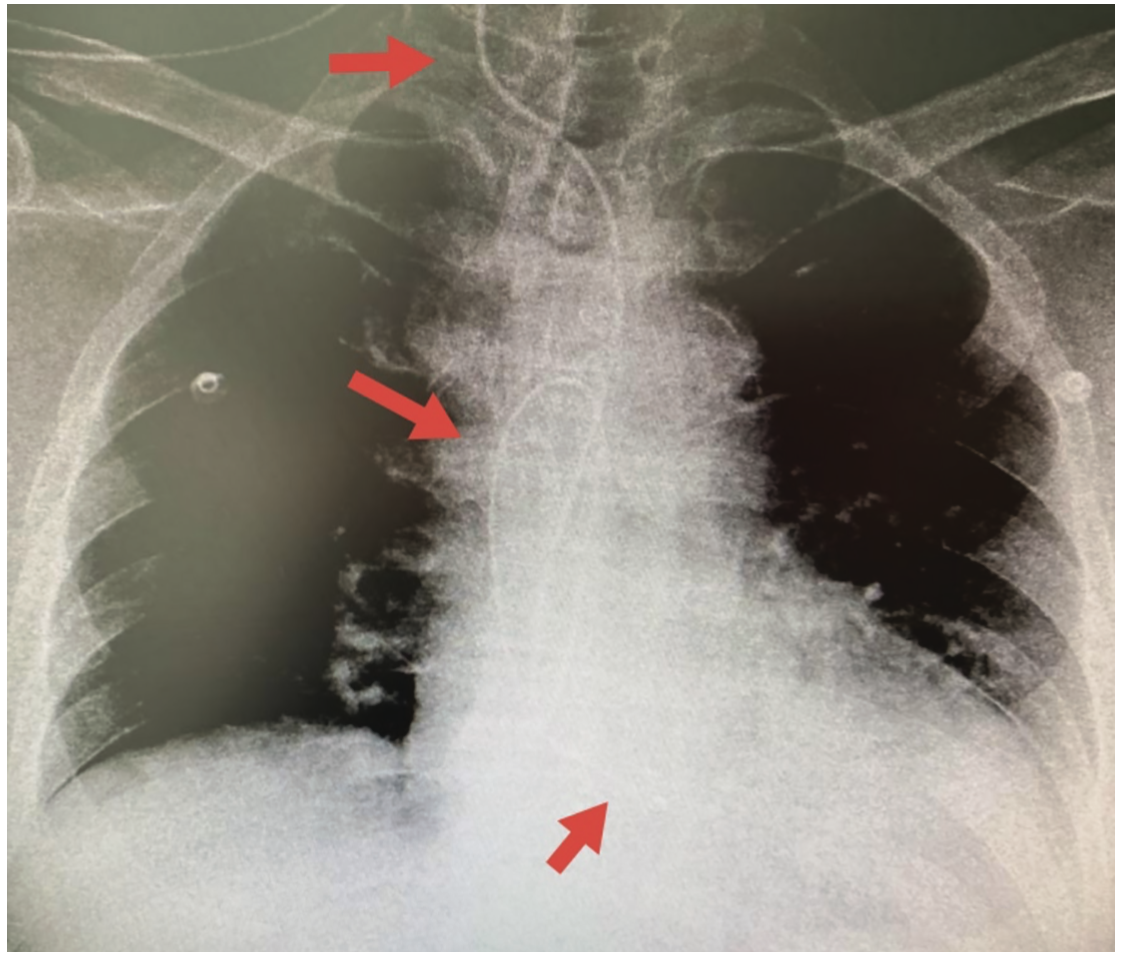

We report the case of a 77-year-old male who underwent temporary pacemaker lead implantation after a symptomatic 2:1 Mobitz type II second-degree block and left bundle branch block conduction (Figure 1). The temporary pacemaker was implanted apparently through the right jugular vein without fluoroscopic guidance, only by monitor guidance. After medical stabilization the patient was referred to our tertiary care center for further management. A cardiovascular system examination was unremarkable. Electrocardiogram showed a paced left bundle branch block pattern; however, with a high threshold stimulation level. The x-ray showed an abnormal lead path (Figure 2). A computed tomography angiography was performed that documented an intra-arterial lead with entry into the right common carotid artery and with the tip crossing the aortic valve and ending in the left ventricular outflow tract (Figure 3). Removal of the lead and relocation of the temporary pacemaker was requested by interventional cardiology. The fluoroscopy showed a temporary pacemaker lead with an arterial course with a loop in the ascending aorta and the tip crossing the aortic valve (Figure 4). A puncture of the right common femoral vein was performed, and a 6 French introducer sheath was placed. The temporary pacemaker lead was advanced to the right ventricle (Figure 5). The intra-arterial lead was removed and an angiogram was performed through the introducer sheath, confirming the arterial site (Figure 6). The introducer sheath was subsequently removed without complications.

In this case, the temporary pacemaker lead was unintentionally malpositioned through arterial access, suspected due to a high threshold stimulation level. An x-ray and computed tomography scan confirmed an abnormal lead path.

Early recognition required careful reading of the 12-lead surface electrocardiogram pacing morphology and other imaging modalities, including chest x-ray, computed tomography, and fluoroscopic images.